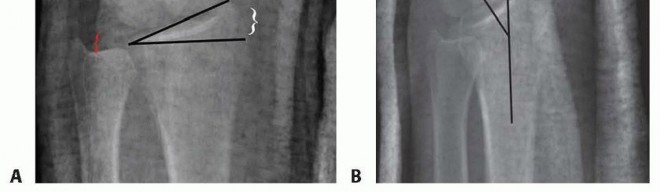

TECH FIG 2 • A. Reduction maneuver. The distal radius is reduced over a bump of towels using traction and palmar displacement of the carpus. B. Plate placement. The plate is placed deep to the EPL and aligned distally over the distal radius. C,D. Reduction imaging. C. PA fluoroscopic view demonstrating final reduction with well-aligned plate. D. Lateral fluoroscopic view demonstrating final reduction with appropriate-length screws and good distal buttressing of the fracture. Volar tilt has been restored. Bone graft is inserted to support reduced articular fragments and then the dorsal plate is applied directly on the radius ( TECH FIG 2B). The plate is first secured with a bicortical screw inserted through the oval sliding hole. Fracture reduction and placement of the plate are confirmed using fluoroscopy. The plate is secured to the distal fragment with one or two cancellous screws. Depending on the implant used, the surgeon should avoid placing the distal ulnar screw through the plate as the prominence of the screw head may irritate the overlying digital extensor tendons in the fourth dorsal compartment.

Additional cortical screws are added in the radius shaft. Reduction and stability are confirmed ( TECH FIG 2C,D). Wound Closure The wound must always be copiously irrigated. The retinaculum is closed deep to the transposed EPL tendon, incorporating the periosteal layer that forms the floor of the extensor compartments ( TECH FIG 3A). The skin is closed with nylon suture ( TECH FIG 3B). Finally, a short-arm volar splint is applied over a sterile dressing. Care should be taken to extend the splint to, but not across the distal transverse palmar flexion crease, in order to reduce the risk of postoperative intrinsic muscle and finger joint contractures.